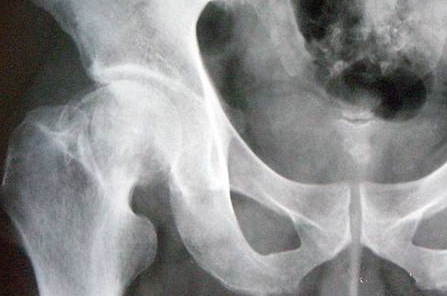

股骨头缺血性坏死做微创介入能治好吗?股骨头坏死专

郑州股骨头坏死医院介绍股骨头缺血性坏死是一种复杂的骨病。目前公认的治疗方法是进行关节…[详情]

股骨头酸痛是怎么一回事呢?郑州骨科专家介绍

郑州骨科专科医院介绍平常所讲的股骨头酸痛是某些患者的自我感觉。如果患者能够明确指出是…[详情]